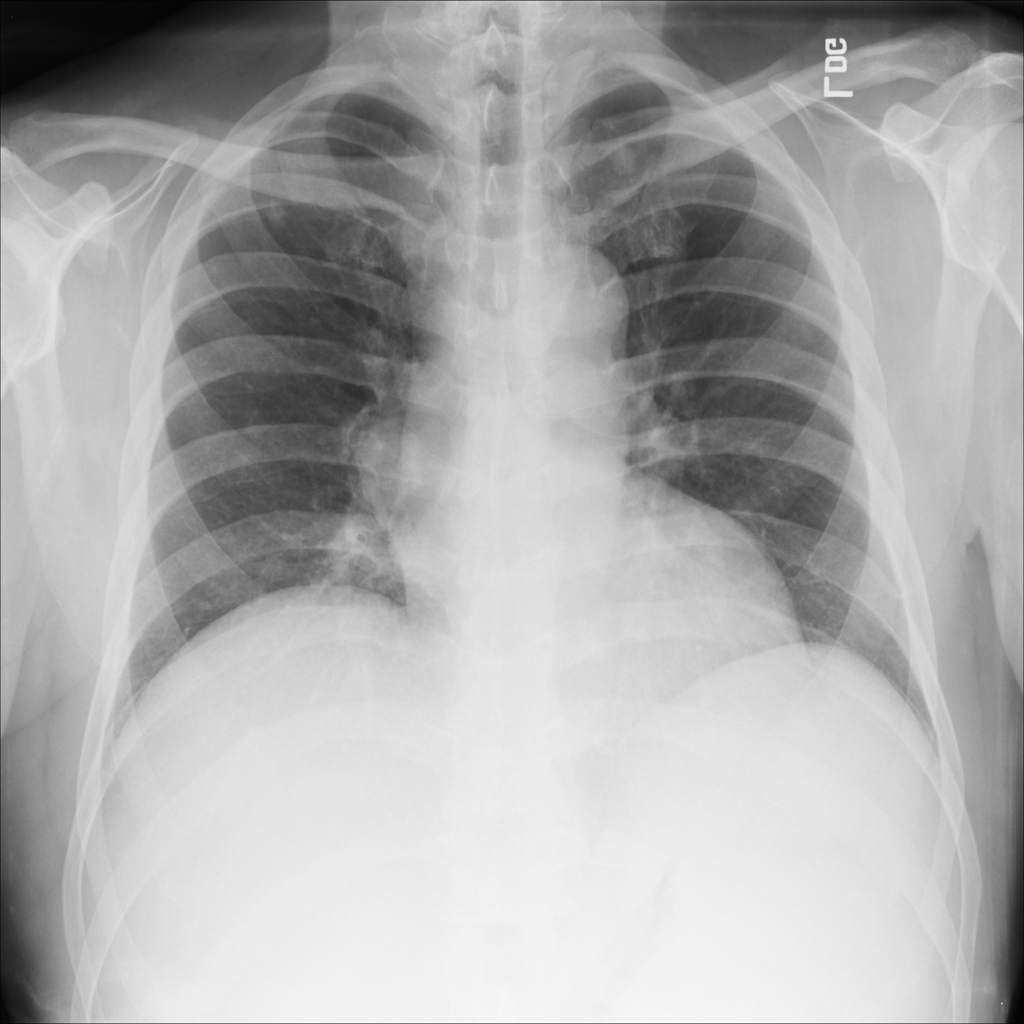

PAT-50E5 · IMG-008Mass

PAT-50E5 · IMG-008

PA